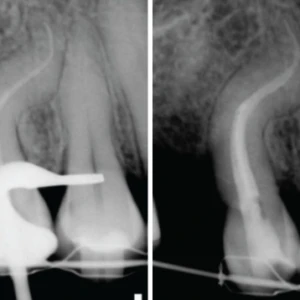

Nishika Canal Sealer BG: Bước tiến mới trong vật liệu trám bít ống tủy

Trong lĩnh vực nội nha, quan điểm về vật liệu trám bít ống tủy đã có một sự thay đổi mang tính cách mạng. Thay vì chỉ sử dụng các vật liệu trơ (inert) với mục đích duy nhất là lấp đầy không gian ống tủy, xu hướng hiện nay là ưu tiên các vật liệu hoạt tính sinh học (bioactive). Những vật liệu này không chỉ trám bít kín khít mà còn tương tác tích cực với các mô xung quanh, kích thích và hỗ trợ quá trình lành thương sinh lý của cơ thể. Đối với các bác sĩ đang có kế hoạch mở phòng khám nha khoa, việc đầu tư vào các loại thiết bị nha khoa và vật liệu cao cấp này không chỉ nâng cao tỷ lệ thành công của ca điều trị mà còn khẳng định uy tín và chất lượng chuyên môn.

Các sealer truyền thống gốc nhựa epoxy như AH Plus, mặc dù có đặc tính cơ học tốt, nhưng về cơ bản là vật liệu trơ và có thể gây ra phản ứng viêm ở mức độ trung bình khi tiếp xúc với mô quanh chóp. Ngược lại, các sealer bioceramic hoạt tính sinh học được thiết kế để tạo ra môi trường thuận lợi cho sự tái tạo mô, hình thành cầu nối khoáng hóa và thúc đẩy quá trình lành thương ở vùng quanh chóp.

Thành phần và cơ chế hoạt động độc đáo của Nishika Canal Sealer BG

Nishika Canal Sealer BG (NBG) là một ví dụ điển hình cho thế hệ sealer nội nha hoạt tính sinh học, dựa trên nền tảng thủy tinh hoạt tính (bioactive glass). Điểm khác biệt cốt lõi của NBG nằm ở công thức độc đáo gồm hai tuýp (paste-paste) và cơ chế đông kết thông qua phản ứng chelat hóa (chelation reaction), thay vì phản ứng hydrat hóa phụ thuộc vào độ ẩm như phần lớn các sealer bioceramic khác trên thị trường.

- Cơ chế đông kết ưu việt: Phản ứng chelat hóa giúp vật liệu đông kết một cách đồng nhất và có thể dự đoán được, không bị ảnh hưởng nhiều bởi sự hiện diện hay thiếu hụt độ ẩm trong ống tủy. Điều này mang lại khả năng kháng rửa trôi vượt trội, đảm bảo sealer giữ nguyên vị trí và duy trì độ kín khít ngay cả trong môi trường ẩm ướt.

Các nghiên cứu in-vitro và in-vivo đã chứng minh hàng loạt ưu điểm của Nishika Canal Sealer BG so với các vật liệu truyền thống:

1. Tương hợp sinh học xuất sắc: NBG chỉ gây ra phản ứng viêm ở mức độ tối thiểu đến nhẹ khi tiếp xúc với mô quanh chóp. Đặc tính này làm giảm đáng kể nguy cơ đau sau điều trị cho bệnh nhân và tạo điều kiện lý tưởng cho quá trình lành thương tự nhiên.

2. Hoạt tính sinh học mạnh mẽ:

- Hình thành Hydroxyapatite (HA): Khi tiếp xúc với dịch mô, NBG giải phóng các ion Canxi và Phosphate, tạo ra một lớp Hydroxyapatite ngay tại giao diện giữa vật liệu và thành ống ngà. Lớp khoáng hóa này không chỉ tạo ra một liên kết hóa học bền vững mà còn bịt kín các ống ngà phụ, tăng cường độ kín khít của hệ thống ống tủy.

- Giải phóng ion Silicate nồng độ cao: Đây là đặc tính nổi bật nhất của NBG. Vật liệu này giải phóng nồng độ ion Silicate cao hơn khoảng 10 lần so với các sealer gốc canxi silicate khác. Ion Silicate đã được chứng minh là có vai trò quan trọng trong việc kích thích các tế bào gốc, thúc đẩy quá trình tạo xương (osteogenesis) và tân tạo mạch máu (angiogenesis). Đây là hai quá trình sinh học cốt lõi cho sự tái tạo và lành thương của các tổn thương quanh chóp.

3. Hiệu quả lâm sàng đã được chứng minh: Dữ liệu lâm sàng cho thấy việc sử dụng NBG giúp giảm đau sau điều trị và mang lại kết quả lành thương tích cực trong dài hạn, ngay cả đối với những ca nội nha phức tạp có tổn thương quanh chóp lớn.